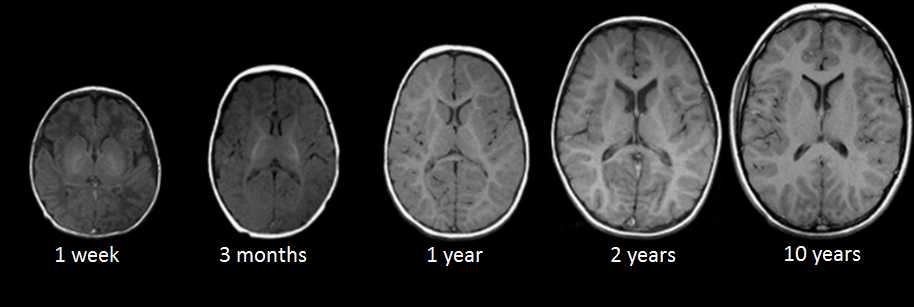

Магнитно-резонансная томография (МРТ):один из самых эффективных методов диагностики заболеваний